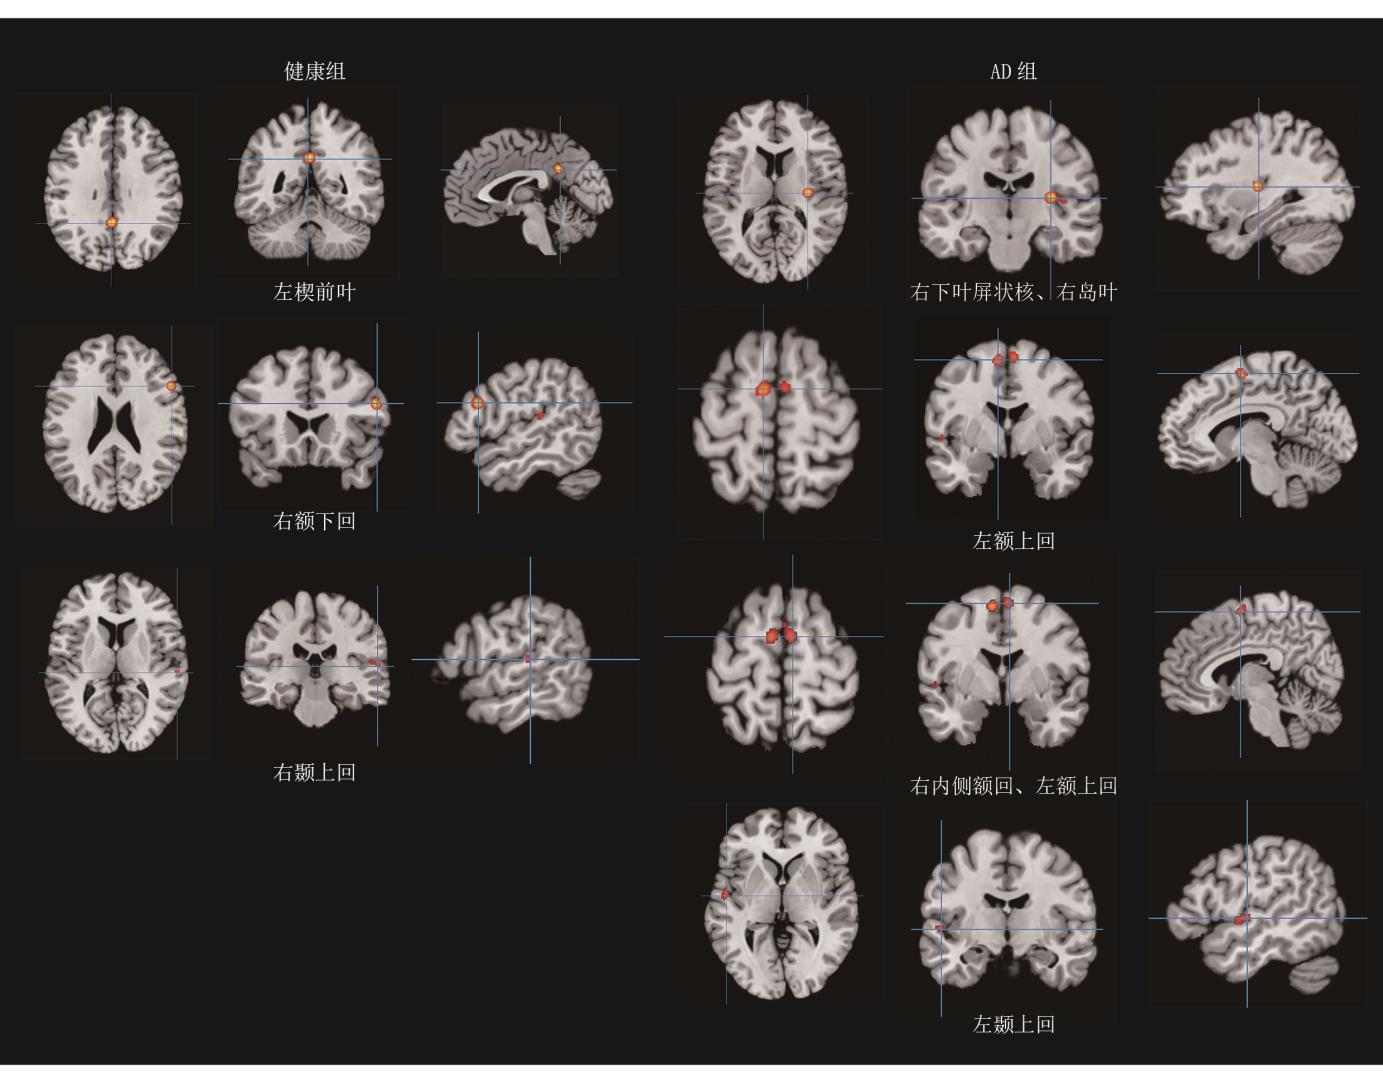

结果 共纳入5项fMRI研究,涉及134例被试,包含99例AD患者,共提取49个激活坐标。健康组的主要激活区域为左侧楔前叶、右侧额下回和右侧颞上回,AD组的主要激活区域则转移至右下叶屏状核及相邻右岛叶、左侧额上回、右内侧额回和左颞上回。AD患者在进行音乐处理时,神经激活模式从高级联合皮质向皮质下结构转移,并伴随额叶激活模式的代偿性改变和顶叶激活的缺失。

Results Five fMRI studies were included, involving 134 participants (99 with AD). A total of 49 activation coordinates were extracted. The main activation regions in the healthy group were concentrated in the left precuneus, the right inferior frontal gyrus and the right superior temporal gyrus, while the primary activated regions in AD group shifted to the right operculum and adjacent right insula, left superior frontal gyrus, right medial frontal gyrus, and left superior temporal gyrus, indicating that during music processing, neural activation patterns in AD patients shifted from higher-order associative cortices to subcortical structures, accompanied by compensatory changes in frontal lobe activation and a loss of activation in the parietal lobe, particularly in the precuneus.